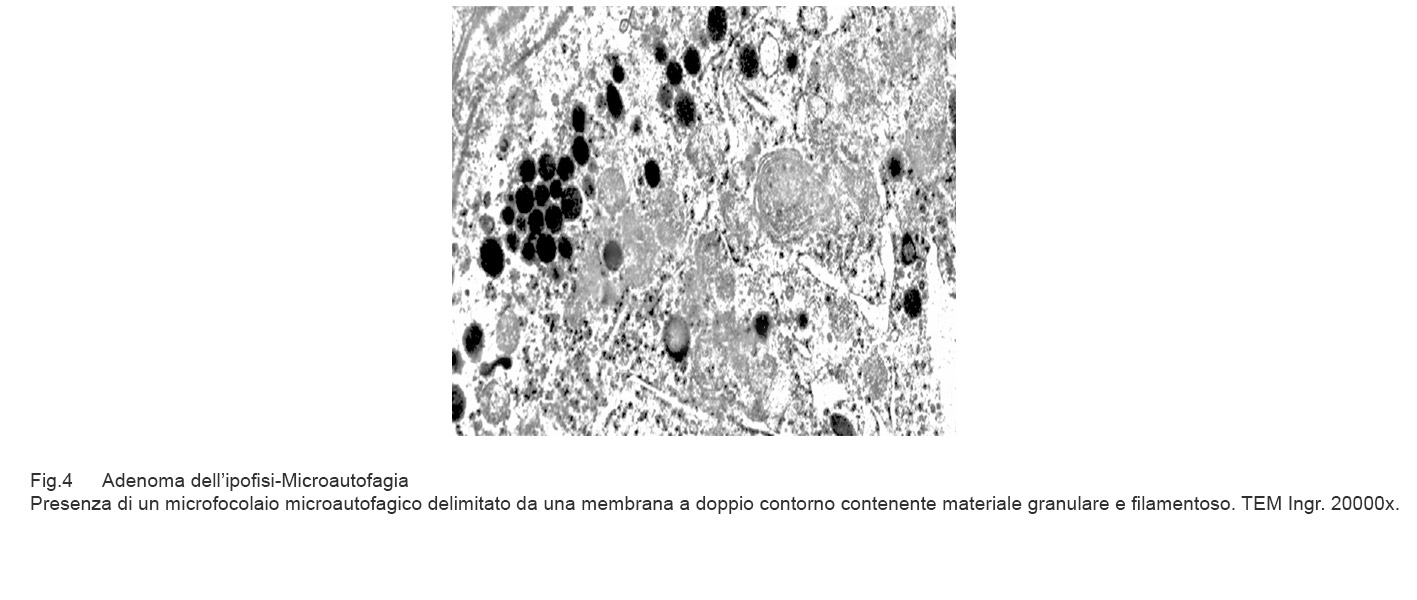

Fig.4  Fig.4a

Fig.4a